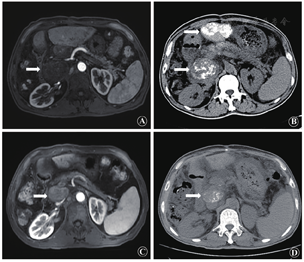

患者男,50岁,主因"原发性肝癌切除术后半年肝内复发并腹膜后淋巴结转移瘤"就诊,2018年3月于我院肝胆外科行肝切除术。术后病理示:肝中-低分化肝细胞癌。2018年9月于我科入院复查,肝脏平扫+增强核磁示:肝左叶新发癌灶,腹膜后肿大淋巴结对比前片明显增大,考虑转移可能(图1A)。化验甲胎蛋白:1 200 μg/L(0~20 μg/L),血常规、生化等指标均在正常范围。诊断:①原发性肝细胞癌,肝动脉化疗栓塞术后,肝癌切除术后;②门静脉癌栓形成;③腹膜后转移瘤;④肝硬化;⑤慢性乙型病毒性肝炎。结合相关影像资料,建议行TACE,术后联合放疗及靶向治疗(肿瘤内科会诊建议仑伐替尼+PD-1),患者拒绝放疗,遂于2018年10月我科行DSA下肝动脉化疗栓塞术。

TACE术后给予保肝、护胃抑酸、预防感染、水化等支持治疗。术后第3天复查腹部平扫CT示:肝左叶新发癌灶及腹膜后淋巴结内可见碘油沉积(图1B)。术后第2周开始口服仑伐替尼靶向治疗(12 mg/次,1次/日),并给予静脉输注PD-1(纳武利尤单抗,200 mg/次,2周/次)。口服仑伐替尼后出现腹泻(+++)、乏力(+++)、体重减轻、皮肤反应(+)、高血压(-)、蛋白尿(+)。术后3个月复查甲胎蛋白:110 μg/L。肝脏增强核磁示:肝内未见新发癌灶,腹膜后淋巴结转移瘤较前明显缩小(图1C)。肺平扫CT纵隔窗示:腹膜后淋巴结转移瘤内可见碘油沉积,较前明显缩小(图1D)。后间隔3个月定期复查至2019年8月,肝内病灶稳定,腹膜后淋巴结转移瘤持续缩小。